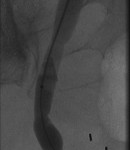

The above images belong to a middle-aged woman with cervical cancer, who developed impaired renal function when the cancer invaded and obstructed her distal ureters. Efforts by urologists to stent her ureters from below through her urethra failed, because the ureteral orifices were invisible. She was referred to the interventional radiology service for ante-grade intervention through the kidneys. Because she was prone on the table for the procedure, there is seeming reversal of her right and left sides.

Access was gained from the back into a dilated posterior calyx of each kidney and secured with a sheath. Antegrade pyelogram on each side revealed marked ureteral and calyceal dilation due to complete obstruction of the distal ureter. A wire was advanced into the urinary bladder past the obstruction, which was dilated with a non-compliant balloon when it resisted the deployment of a nephroureteral stent. The stent was successfully deployed after the balloon dilation.

If obstructions are easy to cross, internal ureteral stents may be placed across them, with one end of the stent in the renal pelvis and the other in the urinary bladder. The stents should be changed periodically through the urethra by urologists or interventional radiologists. Sometimes, as in the patient whose images are displayed above, the obstruction must be predilated to permit insertion of the ureteral stents. Alternatively, a drainage catheter called a nephrostomy catheter can be deployed into the renal pelvis to drain urine into a bag attached to it without crossing the obstruction.